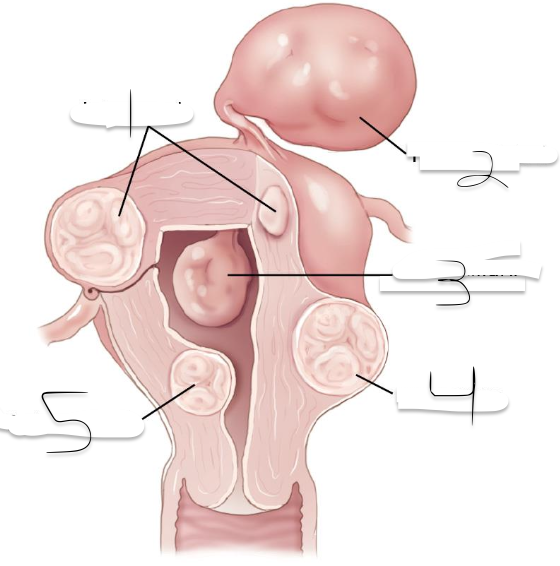

1?

Intramural

2?

Pedunculated

3?

Intracavitary

4?

Suberous

5?

Submuscosal